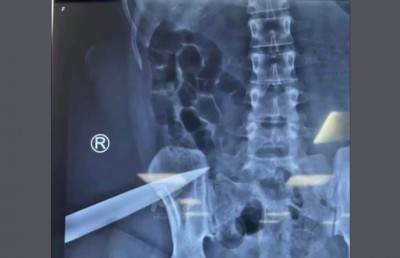

"މިހާރު" އަށް އެނގިފައިވާ ގޮތުގައި އަންހެން މީހާ ހޮސްޕިޓަލަށް ގެންދިޔައީ ވެސް އޭނާގެ ފޫކޮޅުގެ މަސްގަނޑާ ދިމާލަށް ހަރާފައިވާ ވަޅިއާ އެކު، ވަޅި ނުނައްޓަ އެވެ.

އެ ހޮސްޕިޓަލުގެ އިމަޖަންސީގައި އޭނާ އަށް ފަރުވާދެމުން އަންނައިރު މި ވަގުތު އޭނާގެ ހާލަތު ސާފުވާ ގޮތެއް ނުވި އެވެ. އެކަމަކު އަންހެން މީހާގެ ގަޔަށް ވަޅި ހަރާފައިވަނިކޮށް ނަގާފައިވާ އެކްސްރޭއެއް "މިހާރު" އަށް ލިބިފައިވާއިރު ފެންނަނީ އޭނާގެ ޅިނދު ކަށިގަނޑު ކައިރިއަށް ފުންކޮށް ވަޅި ހަރާފައި ހުއްޓަ އެވެ.